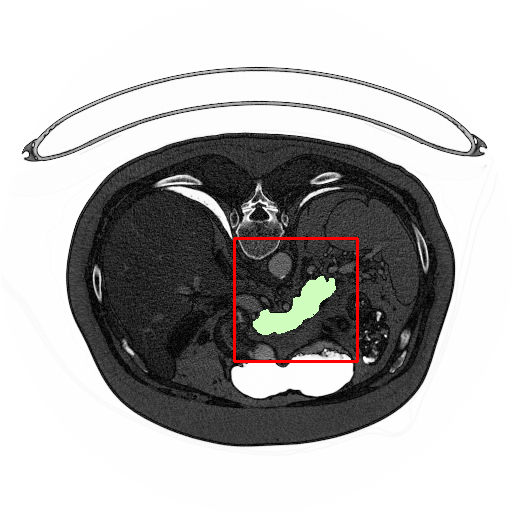

As an important and challenging problem in medical image analysis, pancreas segmentation over a CT volume is typically cast as a voxel-wise classification problem[1], which aims to assign semantic class labels to different CT image regions in a data-driven learning fashion. Usually, such a learning problem encounters numerous difficulties with small-sample-sized training, severe class imbalance, and background clutter with confusing distractions. As shown in Fig  1, a pancreas occupies less than 0.5% fraction of the entire CT volume, and meanwhile has a visually blurry inter-class boundary with respect to other tissues. Furthermore, the pancreas possesses the appearance properties of diverse shapes, various orientations, and different aspect ratios. Such challenging factors often makes the quality of data-driven learning degenerate to extremely biased results (e.g., eroded greatly by non-pancreas regions along with disrupted segmentation results). Therefore, the focus of this paper is on setting up an effective data-driven learning scheme for robust pancreas segmentation with a context-adaptive and environment-interactive pipeline.

Figure 1: Illustration of challenges in pancreas segmentation. The images demonstrates the deformation of pancreas and its tininess in size. The pancreas zones (marked as green) vary in geometrical shape and angle. The smallest pancreas region can be less than 0.1%, and the largest part is no more than 0.8% of the whole slice. Better viewed in color.